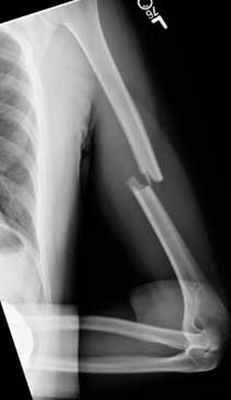

Пациент с оскольчатым переломом среднего отдела плечевой кости.

Выполнена операция: металлоостеосинтез плечевой кости стержнем с блокирующими винтами, введенным ретроградно.

Гипсовая повязка после операции не применялась, сразу после операции начата физкультура для суставов и мышц конечности.

Результат через 4 мес. после операции.

Видно, что мышцы, функция суставов полностью восстановились.